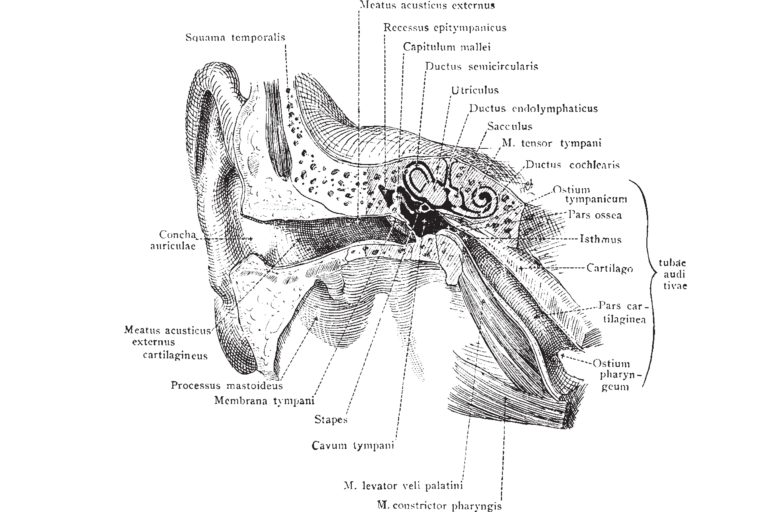

Zum vestibulären System gehören die Teile des Innenohrs und Gehirns, welche die Informationen, die an der Gleichgewichtskontrolle und den Augenbewegungen involviert sind, verarbeiten. Wenn eine Erkrankung oder eine Verletzung diese informationsverarbeitenden Gebiete beschädigen, kann eine vestibuläre Störung entstehen. Vestibuläre Störungen können auch durch genetische Faktoren oder Umweltbedingungen entstehen oder sich verschlimmern. Eine Entstehung aus unbekannten Gründen ist ebenfalls möglich.

Das vestibuläre System besteht aus den Teilen des Innenohrs und Gehirns, die das Gleichgewicht und die Augenbewegungen kontrollieren. Wenn das System durch eine Erkrankung, durch das Altern oder eine Verletzung beschädigt ist, können vestibuläre Störungen entstehen. Diese Störungen werden mit einem oder mehreren dieser Symptome assoziiert, unter anderem:

Spezifische Tests einer vestibulären Dysfunktion

Ein gutes Gleichgewicht und ein klares Sehen sind auf eine enge Verbindung zwischen den vestibulären Organen und den Augen angewiesen. Kopfbewegungen oder andere Stimulationen des Innenohrs, senden über das Nervensystem Signale zu den Augenmuskeln; dies wird „vestibulookulärer Reflex“, kurz VOR, genannt. Der VOR erzeugt normalerweise Augenbewegungen, die für eine klare Sicht bei Kopfbewegungen sorgen.